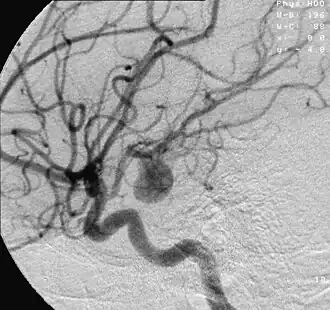

Anévrismes intracrâniens

Leur rupture provoque un accident vasculaire cérébral souvent grave.

Les anévrismes sont particulièrement fréquents au niveau des artères cérébrales, où leur rupture entraîne une hémorragie méningée (qui est un accident vasculaire cérébral).

Avec le temps, l'anévrisme augmente progressivement de diamètre, et comme la tension de la paroi artérielle est proportionnelle au rayon de l'artère (conséquence de la loi de Laplace), le risque de rupture augmente[1]. Le risque de rupture devient menaçant dès un diamètre de 7 mm (pour les anévrismes des artères cérébrales). Lorsqu'il se rompt, l'anévrisme entraîne une hémorragie interne pouvant, si la rupture est importante, rapidement entraîner la mort par compression d'organes vitaux (le cerveau pour les localisations cérébrales, le cœur pour les localisations dans la crosse de l'aorte).